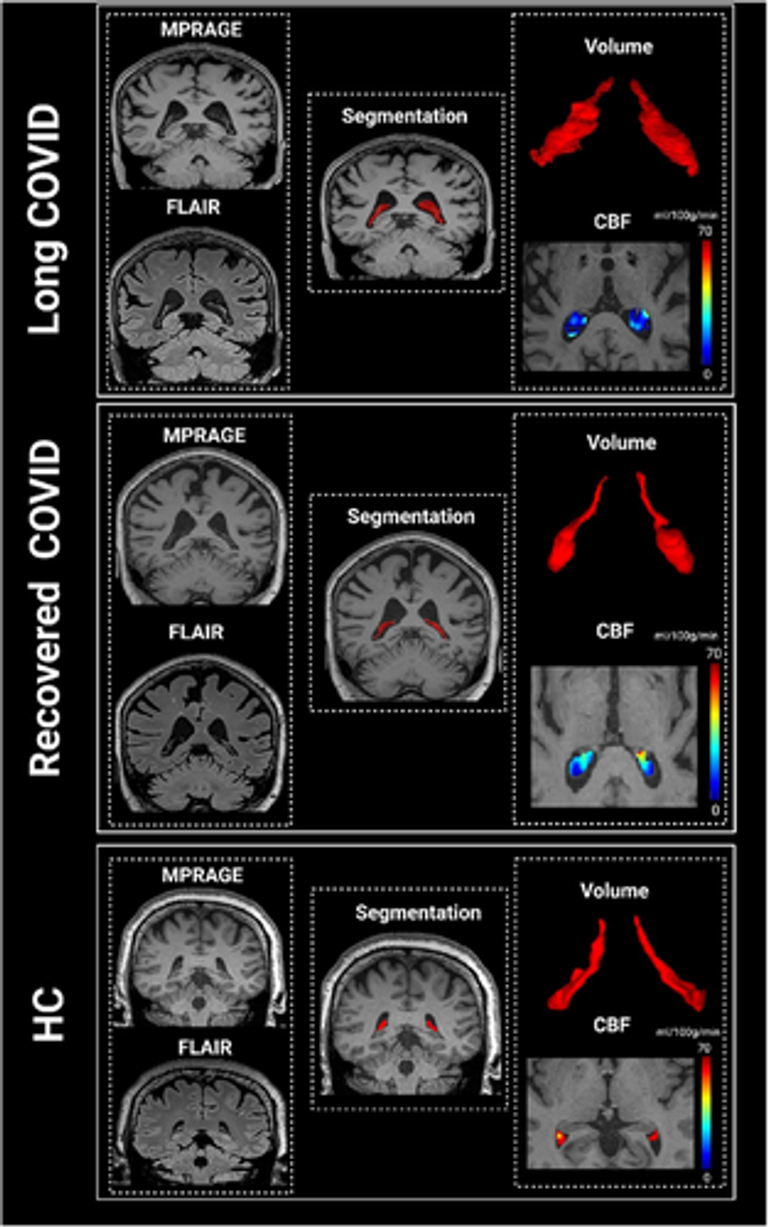

Choroid plexus (ChP) enlargement is a neuroimaging biomarker of neuroinflammation and neurodegeneration. However, evidence of ChP structural and perfusion alterations in long coronavirus disease (COVID) and their clinical relevance remains limited.

This study included 86 long COVID, 67 recovered COVID, and 26 COVID-negative healthy controls (HCs). ChP volume and cerebral blood flow (CBF) were quantified, and their associations with Alzheimer's disease (AD) symptoms and plasma biomarkers were examined.

Both patient groups showed higher ChP volume and lower CBF than HC. Relative to recovered COVID, long COVID patients had a larger ChP volume, but no significant difference in CBF. ChP volume correlated positively with glial fibrillary acidic protein (r = 0.35) and phosphorylated tau217 (p-tau217; r = 0.54), while CBF correlated negatively with p-tau217 (r = –0.56). Both ChP volume and CBF were associated with cognitive decline measured with Mini-Mental State Examination and Clinical Dementia Rating.

These findings suggest that ChP differences in long COVID are associated with AD-related cognitive decline and increased plasma biomarkers.